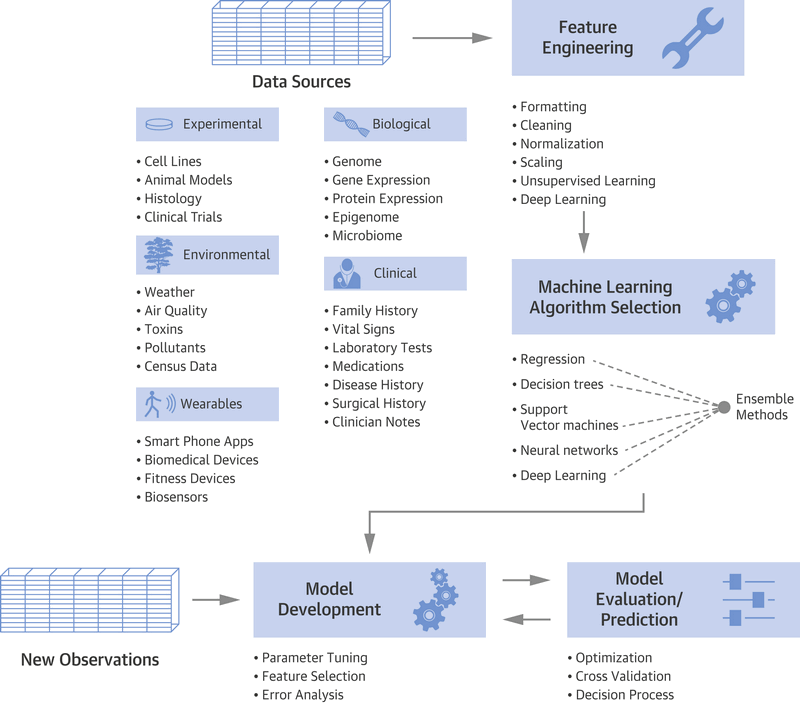

近年来,人工智能技术在医疗保健研究中的使用急剧增加。产生和存储前所未有的大型数据集以及扩大计算规模的能力使AI蓬勃发展。大数据革命最大程度地增强了AI的子领域机器学习(ML),其中学习是通过暴露于预先存在的大型数据集来驱动的。这些发展共同为AI创造了新颖而令人兴奋的机会,可以在多个阶段积极影响医学领域。

受AI影响的医学的另一个主要领域是早期/临床前药物开发,该领域受高失败率困扰,其中超过98%的所有临床前资产在投放市场之前就失败了。随着高通量筛选和基因组技术的出现,研究人员变得更容易获得可以输入到AI框架中的大规模,受控实验数据集。最近,我们的小组和其他研究人员表明AI可以利用庞大而多样的数据集来解决药物开发的多个阶段,例如识别新的靶标或药物候选物,将现有化合物定位为新的适应症或根据预测的不良事件使候选化合物脱险(图1)。

总而言之,我们已经看到了如何使用广泛的AI算法(线性模型,神经网络,NLP等)来利用多种数据类型来解决医学多个方面的问题。